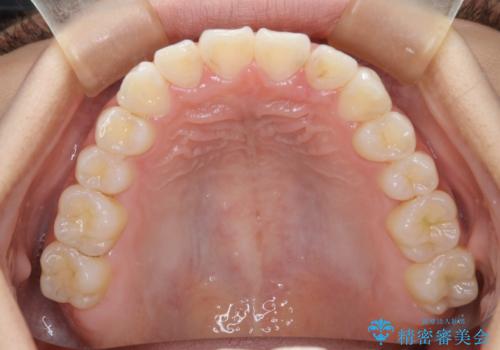

- 前歯の叢生(がたつき)を主訴に来院された患者様です。以前マウスピース矯正をされていたそうでしたが、自身での継続が難しいことなどを理由に、ワイヤー矯正にて改めて矯正治療を希望されました。非抜歯にて治療を計画し治療を行いました。

歯の動きが良く、スムーズに治療を終了しました。一般的にワイヤー矯正はブラッシングが難しいのですが、毎回一生懸命セルフケアをされていたのが印象的です。治療においては、歯の衛生状態も一緒にチェック致します。